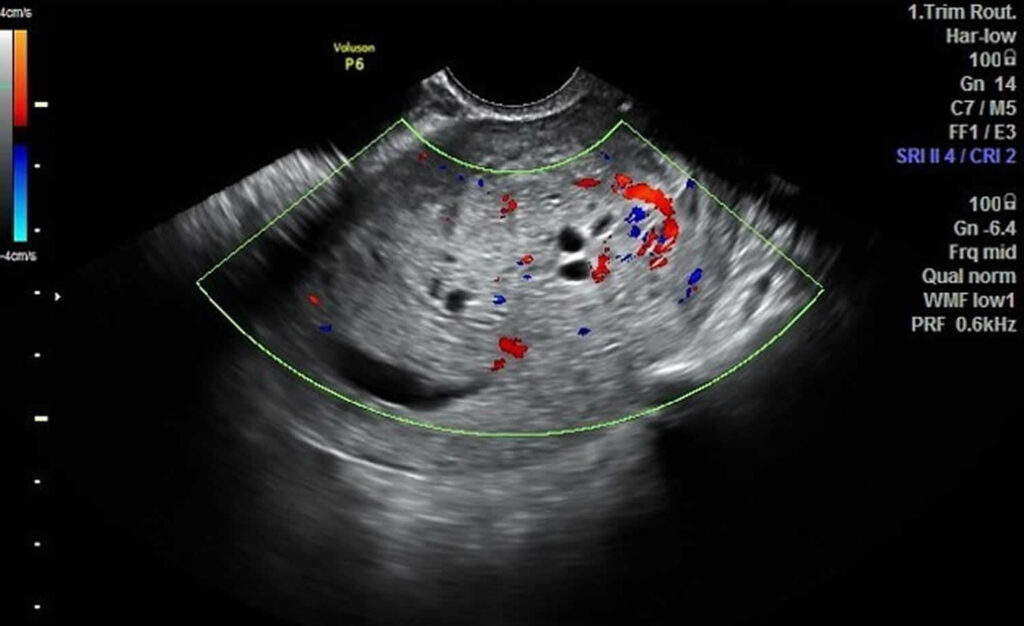

La mola hidatiforme, que como hemos dicho previamente también es llamada “embarazo molar”, es una alteración del embarazo caracterizada por el crecimiento anormal de los trofoblastos, que son las células a partir de las cuales se desarrolla la placenta en condiciones normales.

Existen dos tipos de mola hidatiforme: la completa y la parcial. Hablamos de embarazo molar completo cuando el tejido fetal no llega a desarrollarse en ningún grado y la placenta se encuentra inflamada, tiene un aspecto poco habitual y forma quistes llenos de líquido. En los casos de mola completa en ocasiones ni siquiera se forma la placenta.

Por contra, en la mola hidatiforme parcial es posible observar tejidos placentarios normales, si bien combinados con otros de naturaleza patológica. De hecho puede que incluso se forme parcialmente el feto, si bien éste no podrá sobrevivir a la gestación y lo más probable es que sea expulsado por el organismo de la madre por medio de un aborto espontáneo durante el primer trimestre del embarazo.

En ocasiones pueden observarse un agrandamiento del útero o un crecimiento demasiado rápido del útero en relación al progreso del embarazo, así como quistes en los ovarios o en la vagina. Cabe destacar también la preeclampsia, que se asocia con un incremento de la presión de la sangre y con la presencia de determinadas proteínas en la orina.